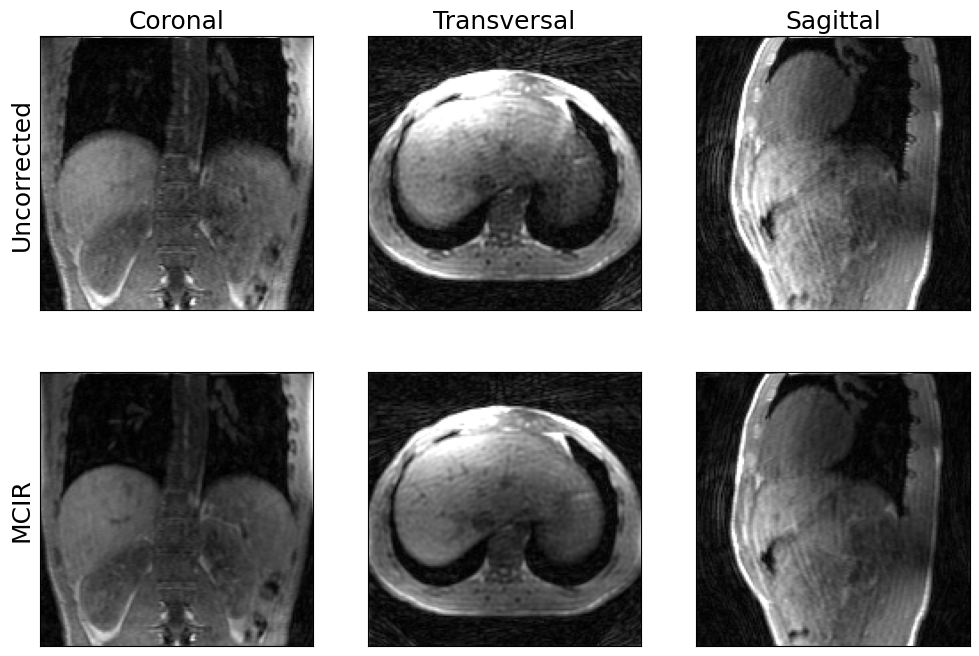

show_views(img.rss(), img_mcir.abs(), ylabels=('Uncorrected', 'MCIR'))

../_images/89815daea42d3f2d20904da294e7c78827f72d4faa98984f148777367da6a177.png